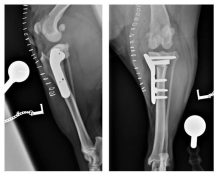

The use of a novel orthopaedic plate in the treatment of a fracture

The use of a novel orthopaedic plate in the treatment of a fracture of the lateral part of the ...